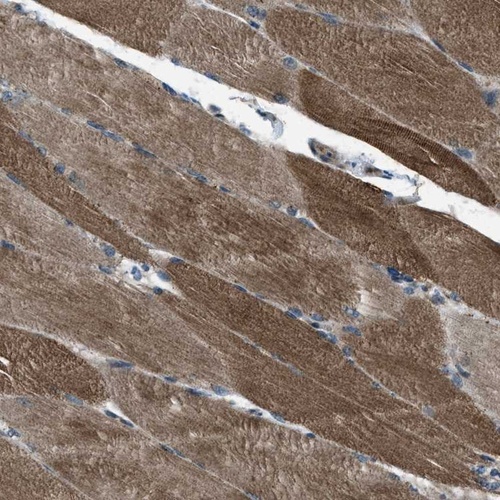

Immunohistochemical staining of human skeletal muscle shows distinct cytoplasmic positivity.